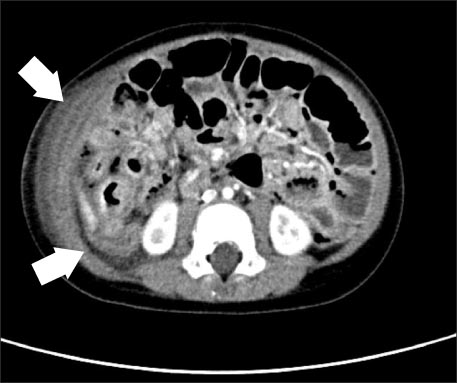

We immediately conducted abdominal X-ray and gastrointestinal ultrasonography for rule out of intussusception. But, there was no evidence of intussusception or appendicitis on gastrointestinal ultrasonography, with small amounts of fluid collection around small and large bowel (Fig. 1).

Fig. 1

Gastrointestinal ultrasonographic images show normal range of appendix intact (diameter 0.5 cm) (A) and intact ileocecal valve (B).

Fig. 1 Gastrointestinal ultrasonographic images show normal range of appendix intact (diameter 0.5 cm) (A) and intact ileocecal valve (B).